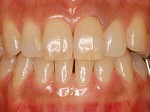

歯をより白く綺麗にしたいと思う方々は多いと思います。審美歯科とは、白い歯が見える口元だけではなく、機能的で歯周組織と顔貌に調和した自然美を追求する治療です。治療は短期間(歯冠修復・ホワイトニングなど)で終わるものから長期に渡る全顎的な治療(歯周病治療・矯正治療・インプラント治療など伴うケース)を行う症例もあります。当院での歯冠修復は

- ジルコニアクラウン修復

- メタルボンドクラウン修復

- グラスセラミッククラウン修復

- ハイブリットインレー、アンレー修復

- コンポジットレジン充填

等の歯冠修復を行っています。